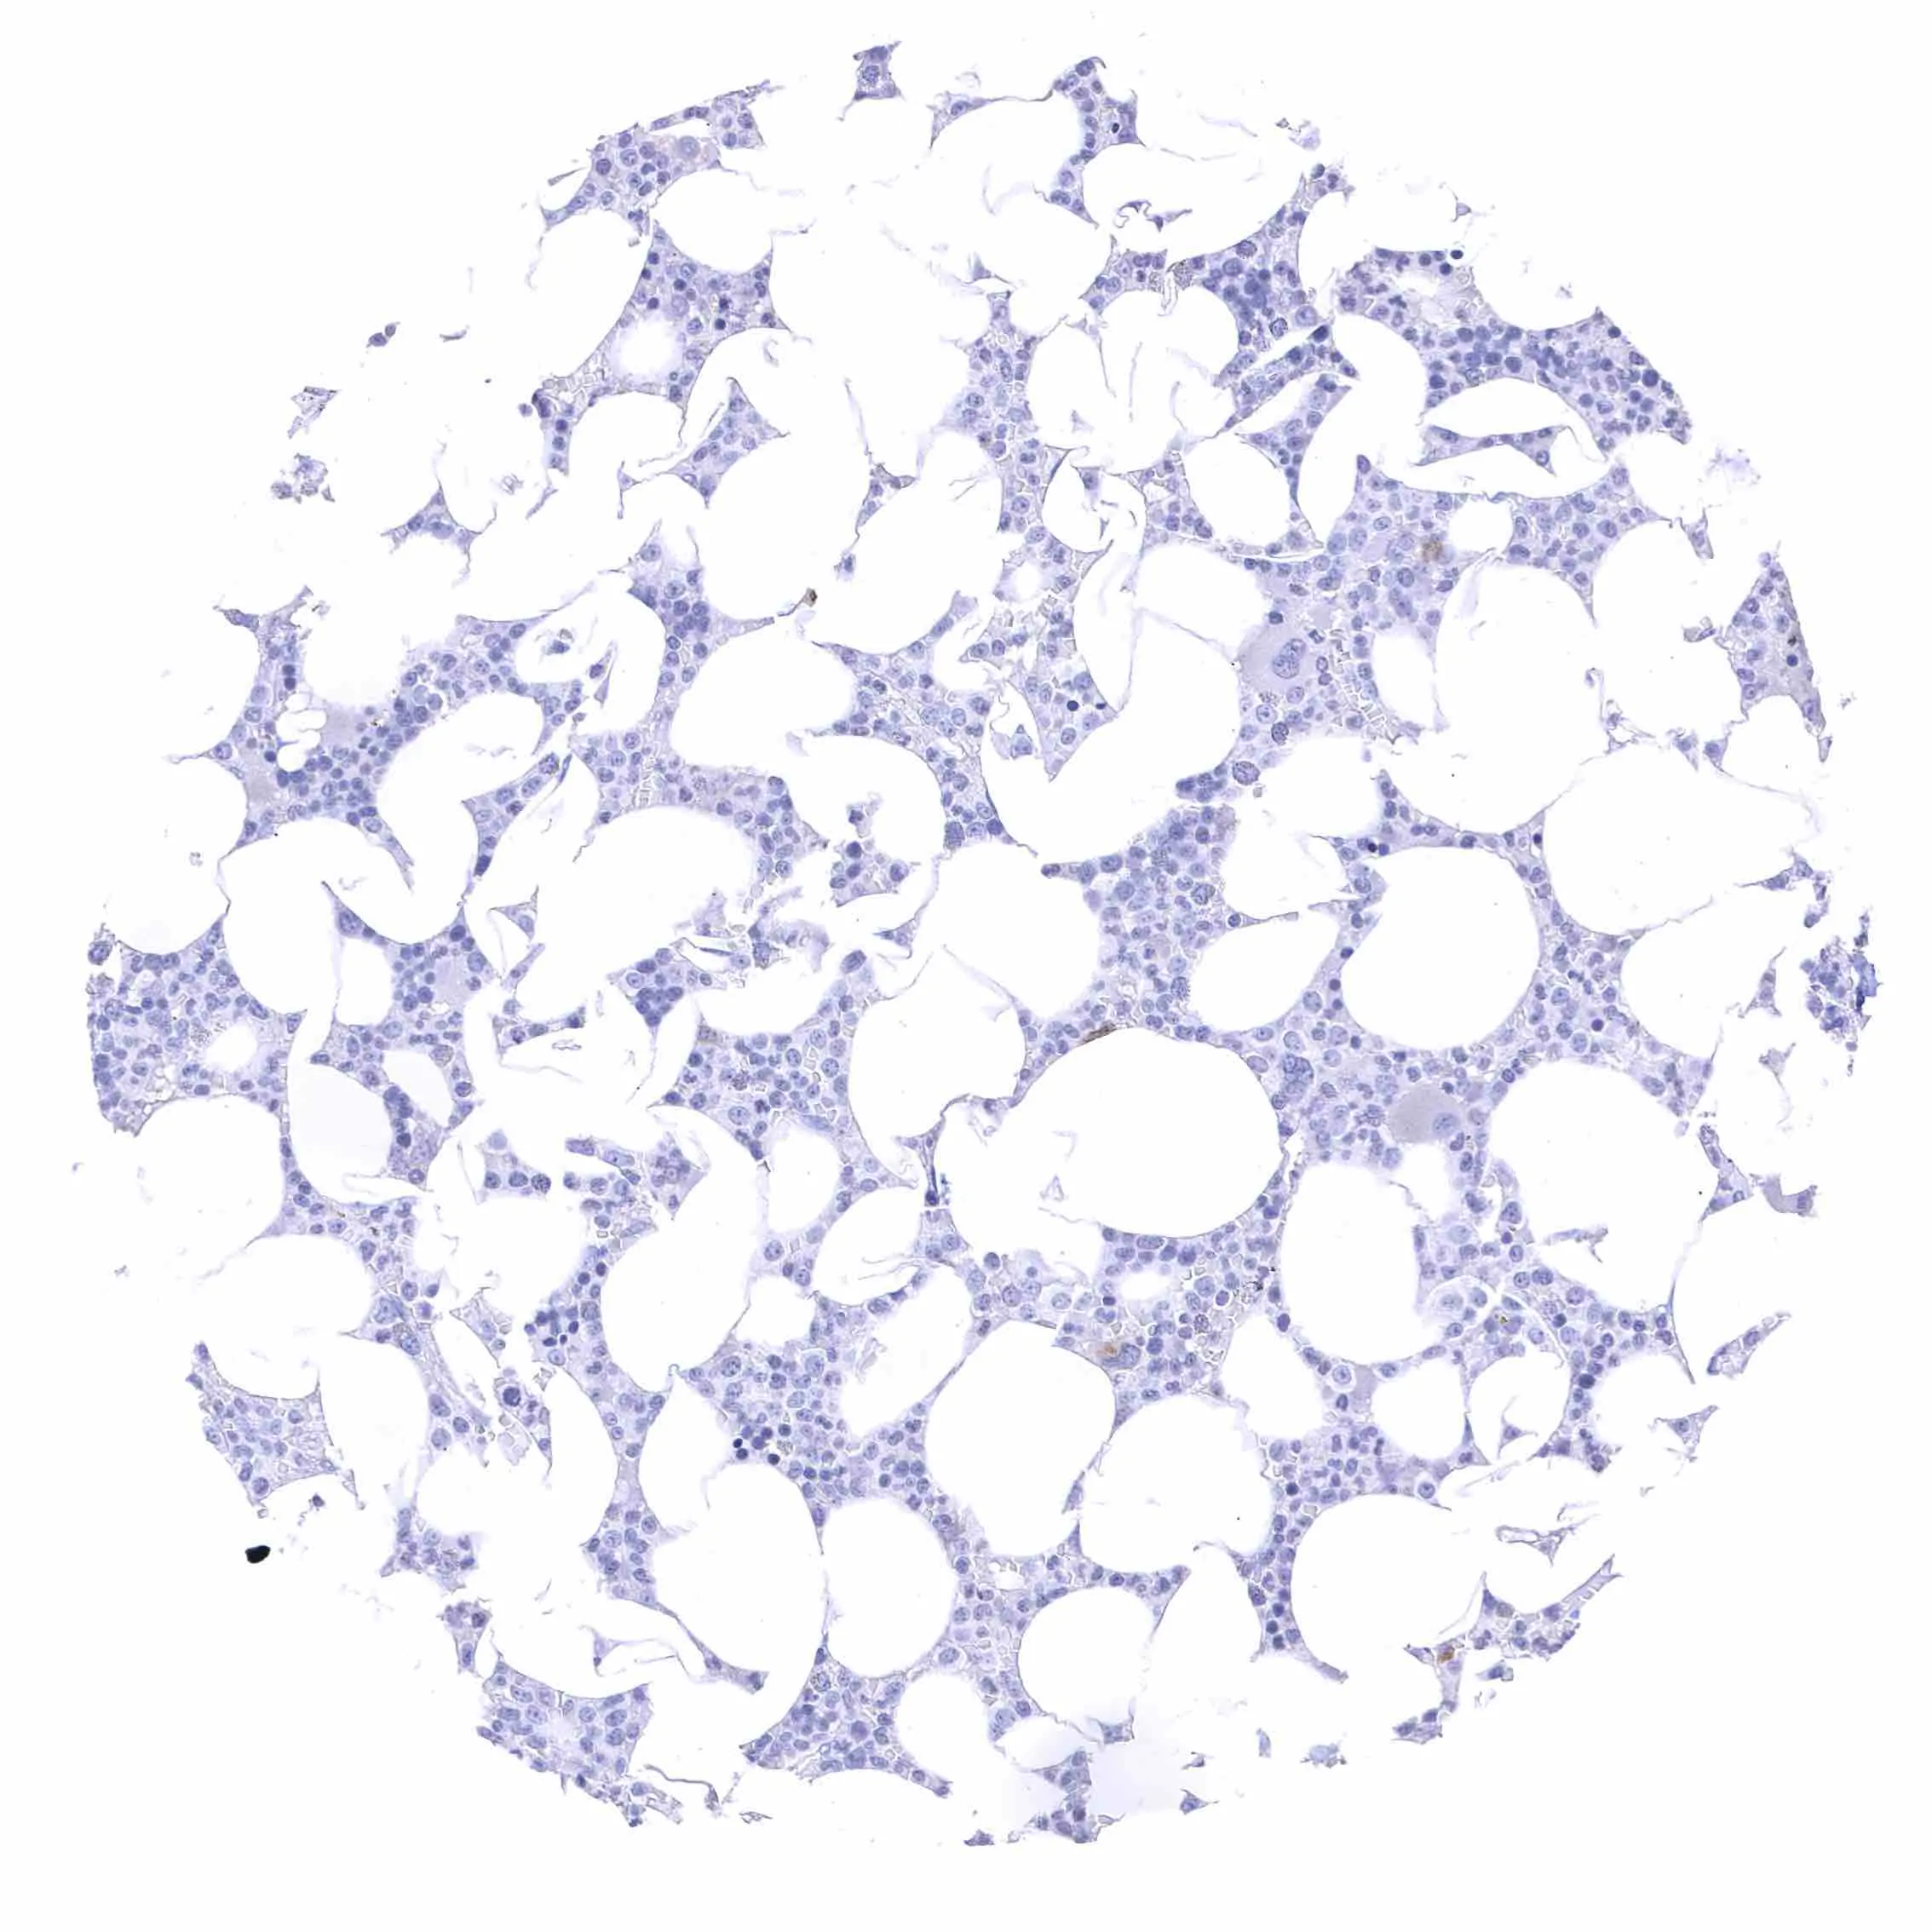

Testis